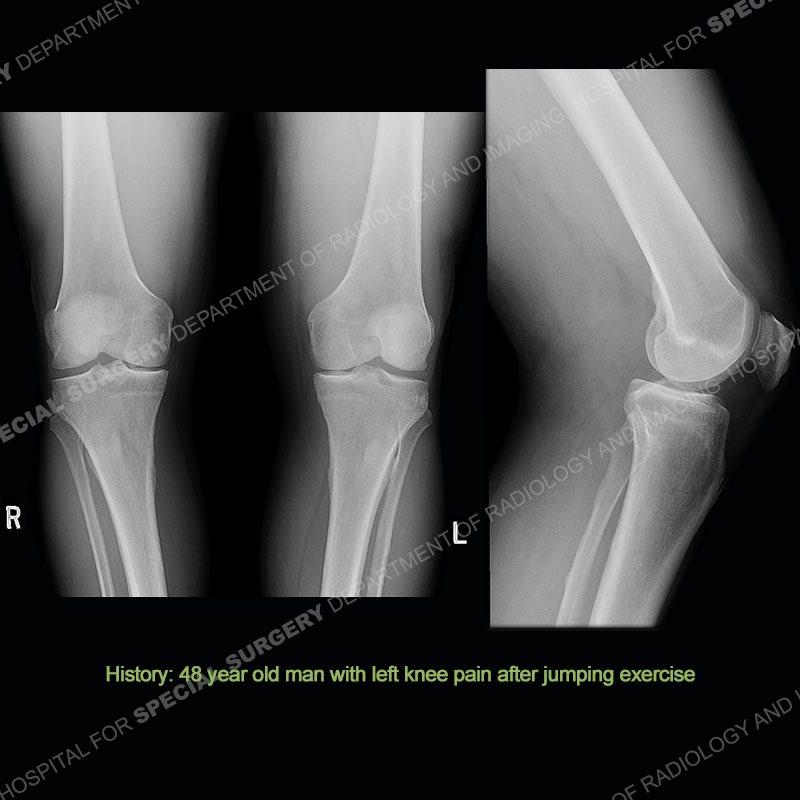

Findings

The radiographs show degenerative change of the medial compartment and a varus knee, but they are not germane to this case. No acute bony injury is present. The MRI shows edema of the posterior medial knee/soft tissue and a focal area of a partially disrupted low signal structure. The details are kept at a minimum in the findings of this case on purpose.